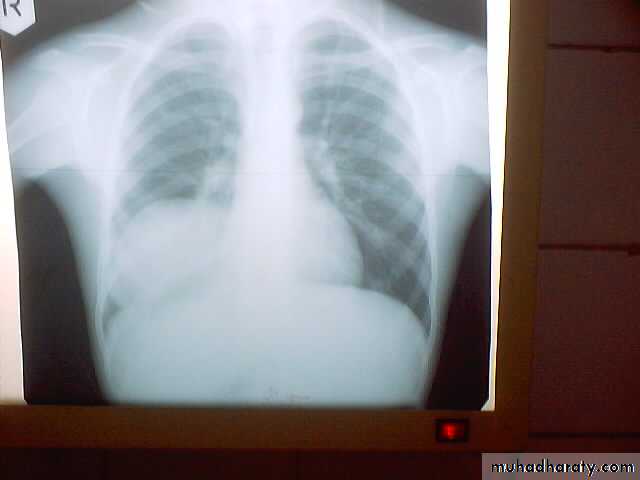

• A-Asymptomatic• Any smooth homogenous opacity of uniform density with clear cut border and little or no reaction around it on a chest X-Ray is a hydatid cyst unless proved the other wise .

• Radiological Findings

• 1-Smooth homogenous opacity (Intact H.C).• 2-Partial rupture (peri-vesicular pneumocyst).